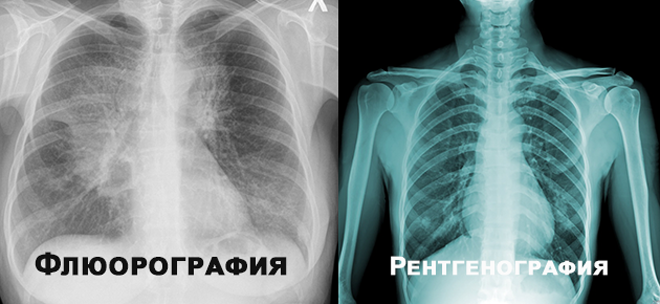

Результативность любой терапии во многом зависит от того, насколько своевременно была выявлена патология. Регулярные диагностические обследования позволяют получить представление о состоянии своего организма. Распространёнными методиками выявления проблем с дыхательной системой являются флюорография и рентген. Процедуры имеют сходные особенности, но между ними есть и разница.

Одна из традиционных методик выявления разнообразных патологий бронхолёгочной системы — рентгенография, отличается высокой информативностью. Её принцип заключается в прохождении сквозь грудную клетку пучка направленных лучей, источник излучения которых находится перед обследуемым. Изображение проецируется на экран, который располагается позади пациента.

Особенностью такой методики обследования как флюорография является направление рентгеновских лучей — они идут со стороны спины, а захват изображения и его отображение происходит спереди грудной клетки.

Методики сходны по своему принципу — при реализации и той и другой обследуемый подвергается воздействию излучения одного вида. Обе используются для выявления патологий органов дыхания.

| Низкая разрешающая способность. Демонстрирует только лёгкие и часть сердца. Позволяет выявить туберкулёз или онкологию. | Высокое разрешение получаемых изображений. Рентгенограмма, помимо выявления туберкулёза или опухоли, позволит определить и другие бронхолёгочные патологии, нарушения в сердце. На ней можно увидеть тромб в лёгочной артерии, абсцесс или другие поражения тканей. |

Можно сделать вывод, что обследования отличаются по степени лучевой нагрузки, периодичности проведения, набору показаний. Помимо этого, рентген применяется не только для обследования грудной клетки, но и с целью диагностики любой части тела. Несмотря на то что доза излучения при рентгенографии больше, она не несёт вред здоровью — при контролируемом применении методики.